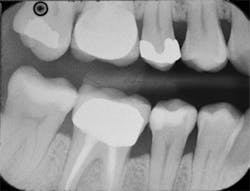

Figure 10: A bitewing radiograph showing the completed restoration on tooth No. 29.

Figure 11: Preoperative view of teeth Nos. 4 and 5. The treatment plan includes composite restorations.